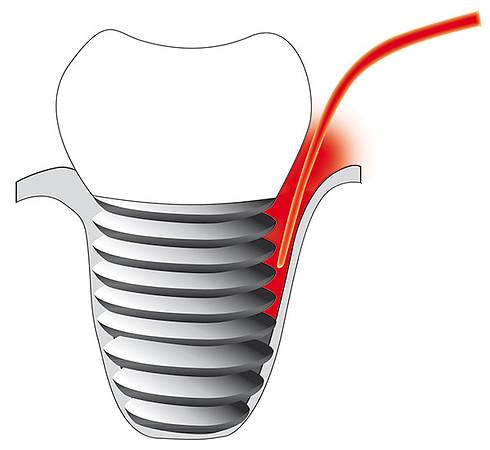

- Implantatentzündung (Periimplantitis)

- Implantatentzündung

© Cumdente